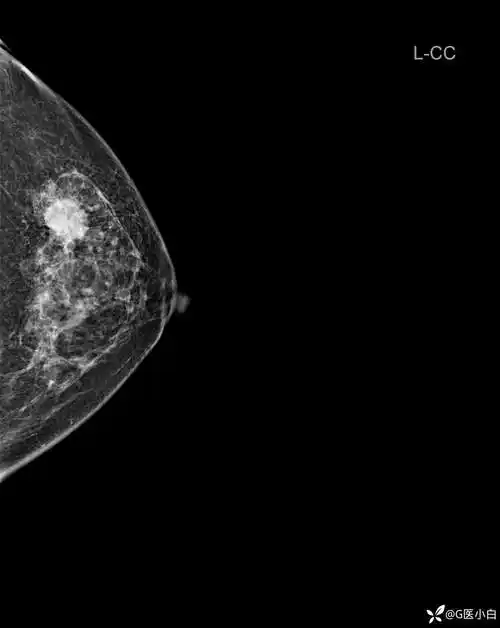

阅乳大师61钼靶篇492402乳腺影像病例发现左乳肿物3月余